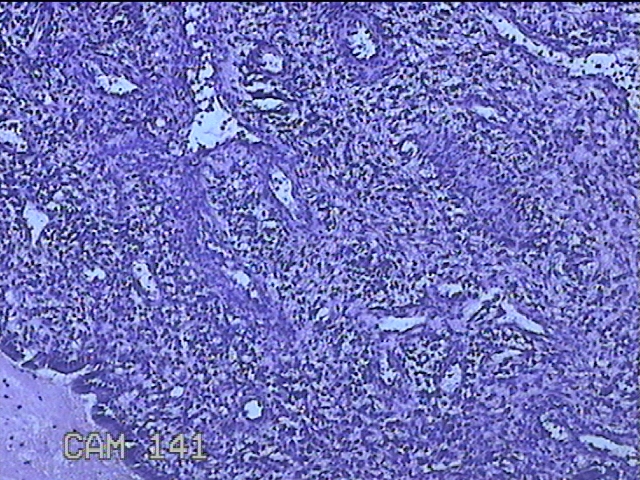

宫颈赘生物

性别

女

年龄

36岁

临床诊断

一般病史

发现宫颈赘生物1个月。

标本名称

大体所见

灰白暗红色肿物1x0.7x0.2cm一个,表面糜烂。

图2